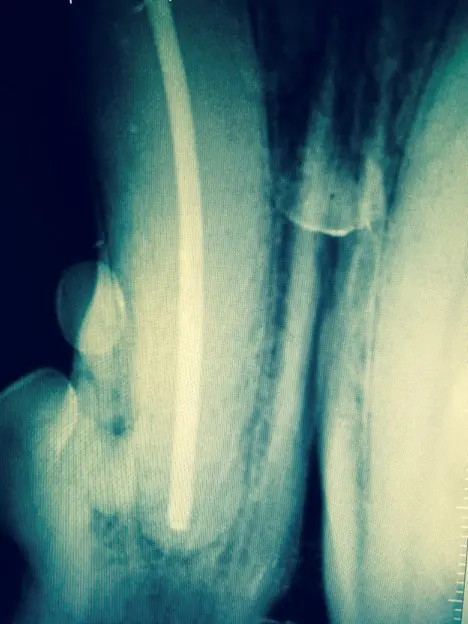

The procedure involves three precise steps performed by a board-certified veterinary dentist and oral surgeon:

- Cleaning the infected canal thoroughly.

- Sterilizing the canal to eliminate bacteria.

- Obturating (filling and sealing) the canal with biocompatible materials.

The materials used in veterinary root canal therapy are the same high-quality products used in human dentistry, as few specialized veterinary options exist.